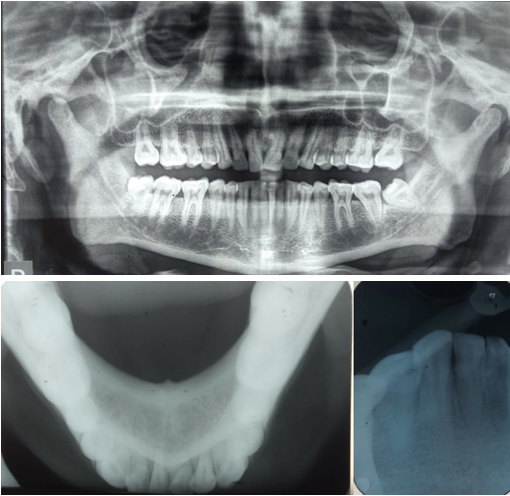

We made a differential diagnosis of Periperal ossifying fibroma, haemangioma, extravasation mucocele, giant cell epulis, soft tissue fibroma. To narrow down our diagnosis patient several investigations were performed. Patient was advised orthopantomogram, occlusal radiograph in relation to mandible and IOPAR in relation to 42 and 43. Radiographic investigations revealed no periapical or periodontal involvement and no calcifications in the region as well. The ultrasonograpy of the soft issue lesion showed a vascular lesion in the vestibule of the mouth with both arterial and venous flow patterns. The patient was advised FNAC and excisional biopsy.

Radiographic investigations